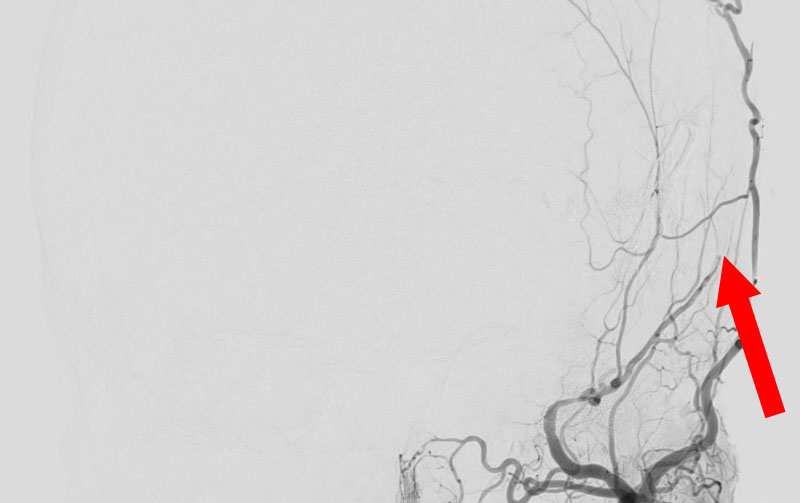

1586

'25年10月6日

硬膜動静脈瘻

40代

大阪府の病院

手術写真

治療

前